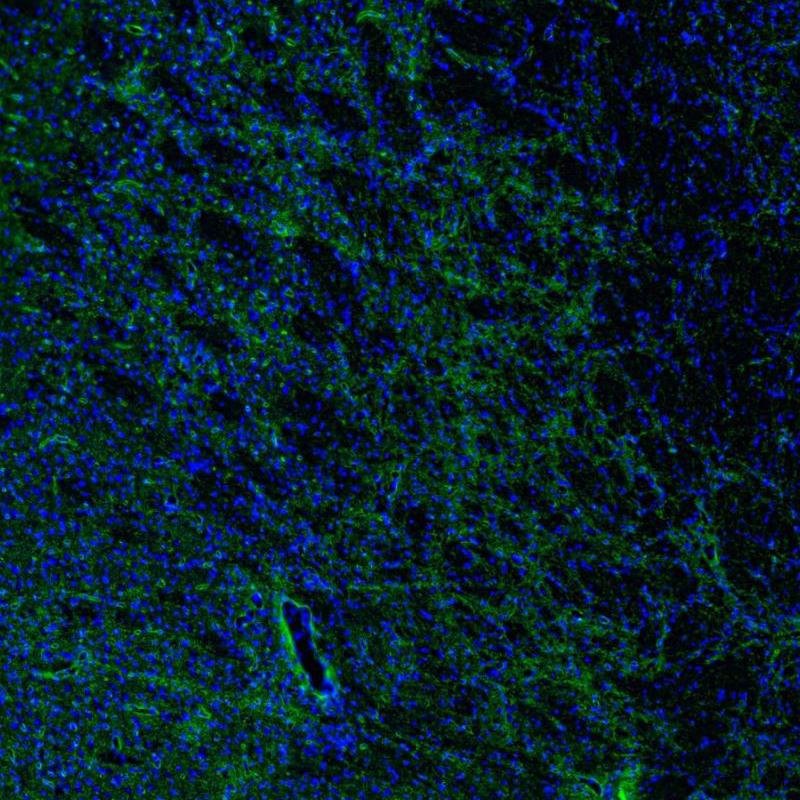

Immunohistochemistry analysis in human cerebral cortex and liver tissues using HPA014784 antibody. Corresponding AQP4 RNA-seq data are presented for the same tissues.

The Anti-AQP4 antibody (HPA014784) specifically targets Aquaporin 4 (AQP4), a vital water channel protein primarily expressed in the brain and spinal cord. AQP4 plays a crucial role in maintaining water homeostasis and is significant in various physiological and pathological processes.